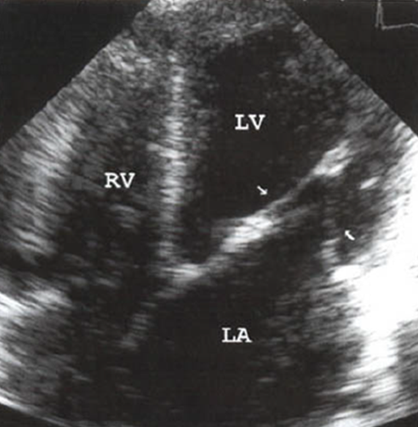

what is this?

parachute mitral valve